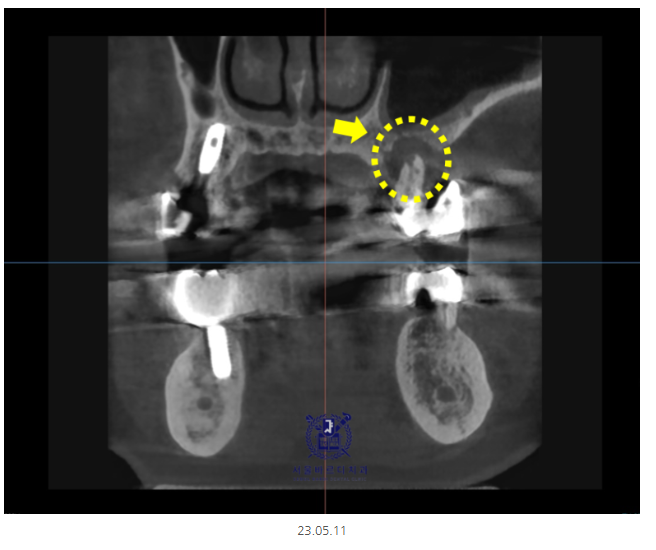

미사 임플란트를 위해 ct 촬영을 시행하였습니다.

x-ray 상에서 까맣게 보이는 부분이

뼈가 녹은 부분입니다.

잇몸 뼈가 많이 녹은 상태라

발치를 하면서 뼈이식이 동시에 진행되었습니다.